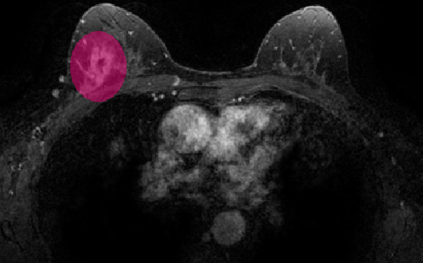

Most papers caution against using predictive models for disease stratification based on unselected radiomic features, as these features are affected by contouring variability. Instead, they advocate for the use of the Intraclass Correlation Coefficient (ICC) as a measure of stability for feature selection. However, the direct effect of segmentation variability on the predictive models is rarely studied. This study investigates the impact of segmentation variability on feature stability and predictive performance in radiomics-based prediction of Triple-Negative Breast Cancer (TNBC) subtype using Magnetic Resonance Imaging. A total of 244 images from the Duke dataset were used, with segmentation variability introduced through modifications of manual segmentations. For each mask, explainable radiomic features were selected using the Shapley Additive exPlanations method and used to train logistic regression models. Feature stability across segmentations was assessed via ICC, Pearson's correlation, and reliability scores quantifying the relationship between feature stability and segmentation variability. Results indicate that segmentation accuracy does not significantly impact predictive performance. While incorporating peritumoral information may reduce feature reproducibility, it does not diminish feature predictive capability. Moreover, feature selection in predictive models is not inherently tied to feature stability with respect to segmentation, suggesting that an overreliance on ICC or reliability scores for feature selection might exclude valuable predictive features.